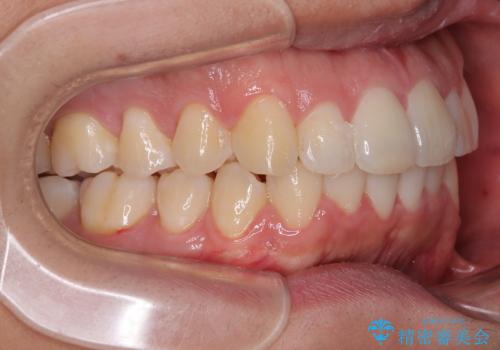

前方に捻れた前歯を治したい インビザライン矯正治療

- 前歯のデコボコを治したいとのことで来院された患者様です。

上下顎ともに歯列全体の後方移動とIPR(歯と歯の間を削る)によってデコボコが解消するように設計し、インビザラインにより治療を行うこととしました。